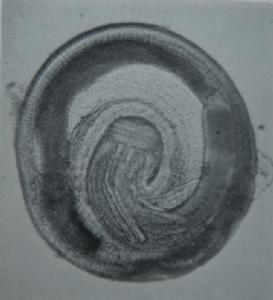

成蟲短粗,活時呈鮮紅色,稍透明兩端稍向腹面彎曲,前斷為球形,上有8圈下鉤,頸部狹窄,提前半部和尾端處被有很多體棘,體棘的形態有分類學意義,雄蟲長11—25mm,雌蟲長25—54mm。蟲卵橢圓形,一端有帽狀透明塞,內含1—2個卵細胞。第三期幼蟲盤曲呈6字形,長約4mm,頭頂部具唇,頭球上都具4環小鉤,其數目和形狀有重要的蟲中鑑別意義,全身被有200例以上的單齒皮棘,體前部的棘長10μm,往後逐漸變小,變稀,在體前1/4的體內有4個肌質的管狀頸囊,各自開口於球內的氣室中,內含漿液,這四個構造對頭球的膨脹和收縮有重要作用,食管分為肌性和腺性兩部分。